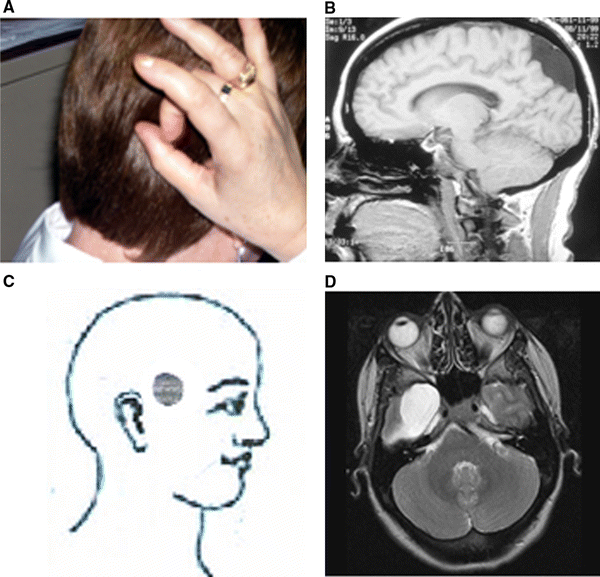

From thejournalofheadacheandpain.biomedcentral.com

Nummular headache associated to arachnoid cysts The Journal of Dysesthesia Migraine Plaguing humans for more than two millennia, manifest on every continent studied, and with more than one billion patients having an attack in any. Migraine treatment involves acute (abortive) and preventive (prophylactic) therapy. There are four types of primary headache: Patients with frequent attacks usually require both. It may have continuous and/or episodic. Migraine headaches can be provoked by surgical. Dysesthesia Migraine.